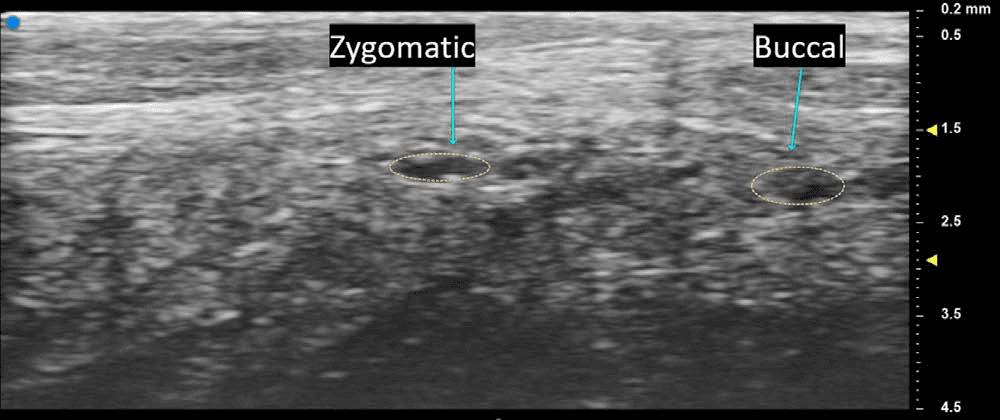

안면신경의 관골지(zygomatic branch)와 협부지(buccal branch)를 축상면 초음파로 명확하게 구분하여 관찰할 수 있었으며, 각 분지가 서로 다른 층에서 주행하는 모습이 실시간으로 구별되어 나타났습니다.

안면마비 - 안면신경의 관골지(zygomatic branch)와 협부지(buccal branch)를 축상면 초음파로 명확하게 구분하여 관찰한 영상입니다. 두 Figure 4. 안면신경의 관골지(zygomatic branch)와 협부지(buccal branch)를 축상면 초음파로 명확하게 구분하여 관찰한 영상입니다. 두 신경 분지가 서로 다른 층에서 주행하는 모습이 초음파를 통해 선명하게 구별되어 나타나고 있습니다. 이러한 개별 신경 분지의 정확한 식별은 안면 거상술이나 기타 안면 수술 시 특정 기능 영역의 신경 손상을 최소화하는 데 중요한 정보를 제공합니다.